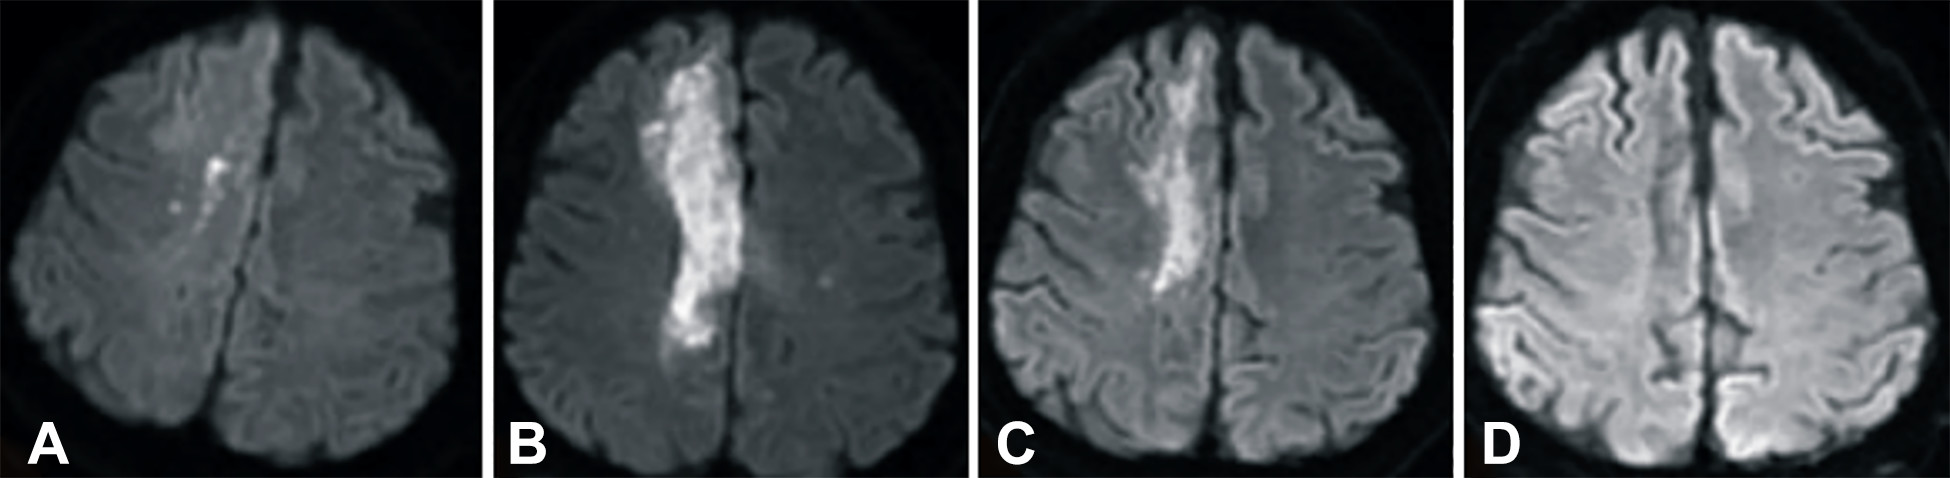

發病后2小時和8天行彌散加權成像(DWI)檢查,發現右側放射冠梗塞(白色信號增加),3個月后梗塞散在,6個月后消失(圖2A-D)。

卒中發病后2小時和單核細胞臍帶血輸注后6個月獲得的彌散加權圖像

圖2 . 卒中發病后2小時和單核細胞臍帶血輸注后6個月獲得的彌散加權圖像。(A)卒中后2小時,(B)臍帶血輸注后1天,(C)臍帶血輸注后3 個月,(D)單核細胞輸注后6個月